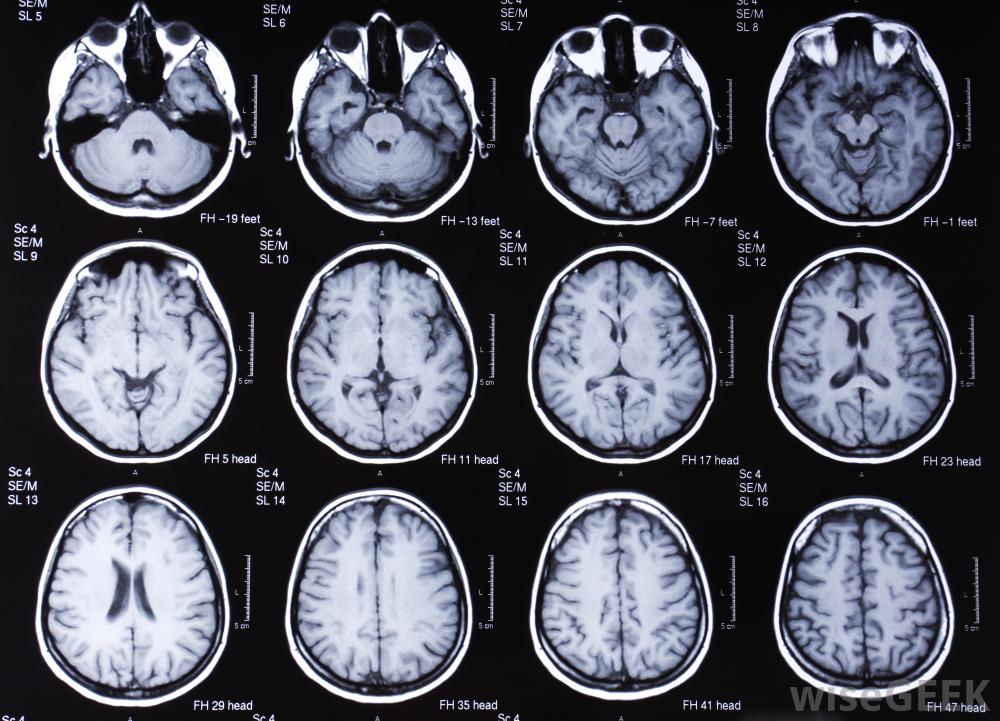

腦部核磁共振掃描可幫助確定腦震蕩的嚴重程度。